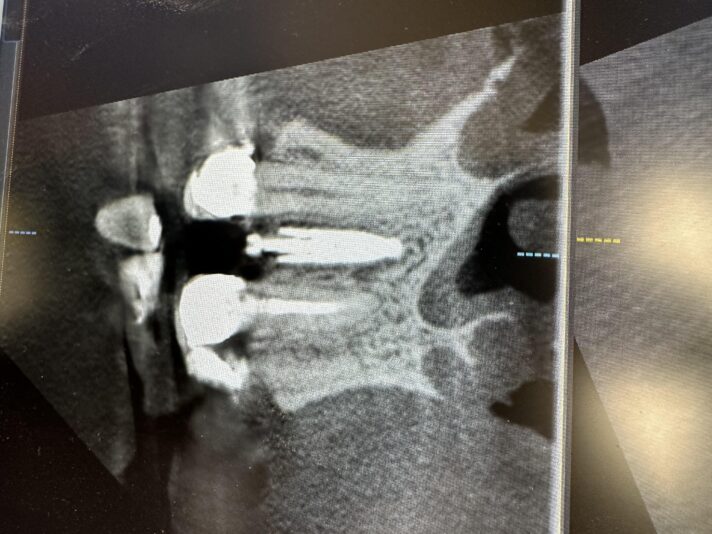

• Looks good, right?!? Not once you see the cbct and create a larger full thickness flap. What would you do here? What are your options? This happened during one of our live surgery courses. Please leave a comment below on what you would do and a couple options we may have. After I recieve several comments I will post a follow up post next week…

Read more

• implant position looks too buccal to me in this photo. i’d remove and start a new osteotomy and sink the implant to the level of the lingual bone

1